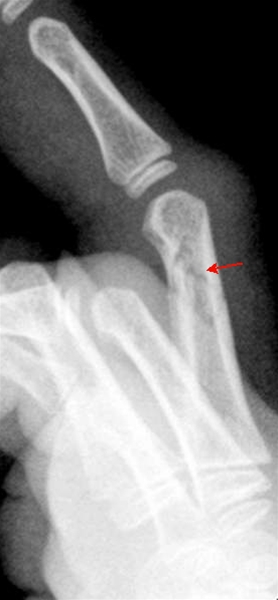

Phalanx-fraktur - sidebillede

Fraktur i 3. fingers proksimale phalanx uden fejlstilling i dette plan. Der skal altid foretages røntgenundersøgelse i to projektioner, for at stillingen kan bedømmes.